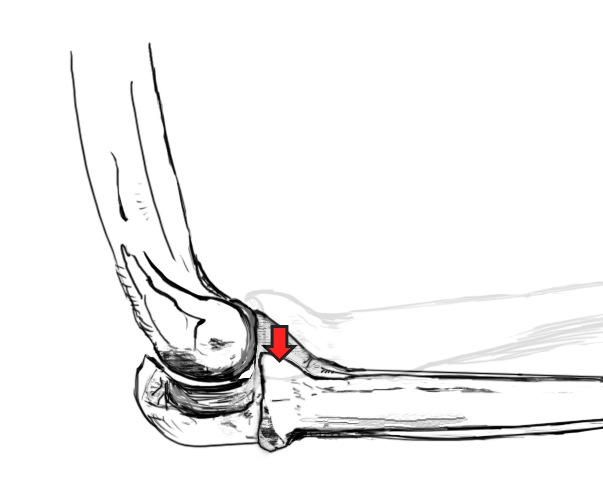

Posterolateral Rotatory Instability

Definition

Radius rotates externally in relation to the ulna

- posterior displacement of the radial head relative to the capitellum

- in flexion